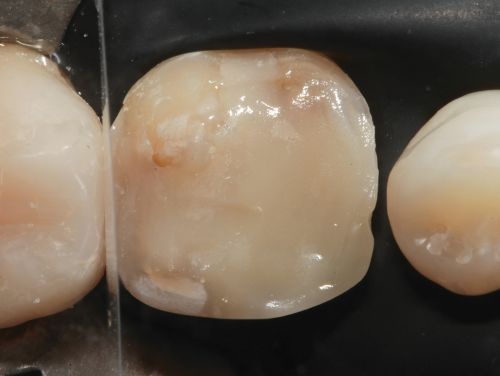

A 35-year-old male presented to the clinic to replace some inadequate restorations, one of which was for the lower right first molar (Fig. 1). For this tooth, the molar was restored with composite resin using the direct technique. The operative field was isolated, the old restoration was removed, and surface hybridization was completed using Futurabond U universal adhesive from Voco (Fig. 2). After placing a sectional matrix and a spacer ring, the composite resin (Voco’s GrandioSO 4U, shade A2) was placed in the proximal box with a thickness less than 4 mm, which is the maximum recommended thickness for the chosen material (Fig. 3). Additional increments of composite resin were applied to complete the anatomical stratification. The final morphology was sculpted, followed by light-curing to ensure complete polymerization (Fig. 4). The rubber dam was removed (Fig. 5), and the occlusion was adjusted using a finishing carbide bur with 12 blades (Fig. 6). Finishing and polishing was completed, with the final result shown in the Figures 7 and 8.